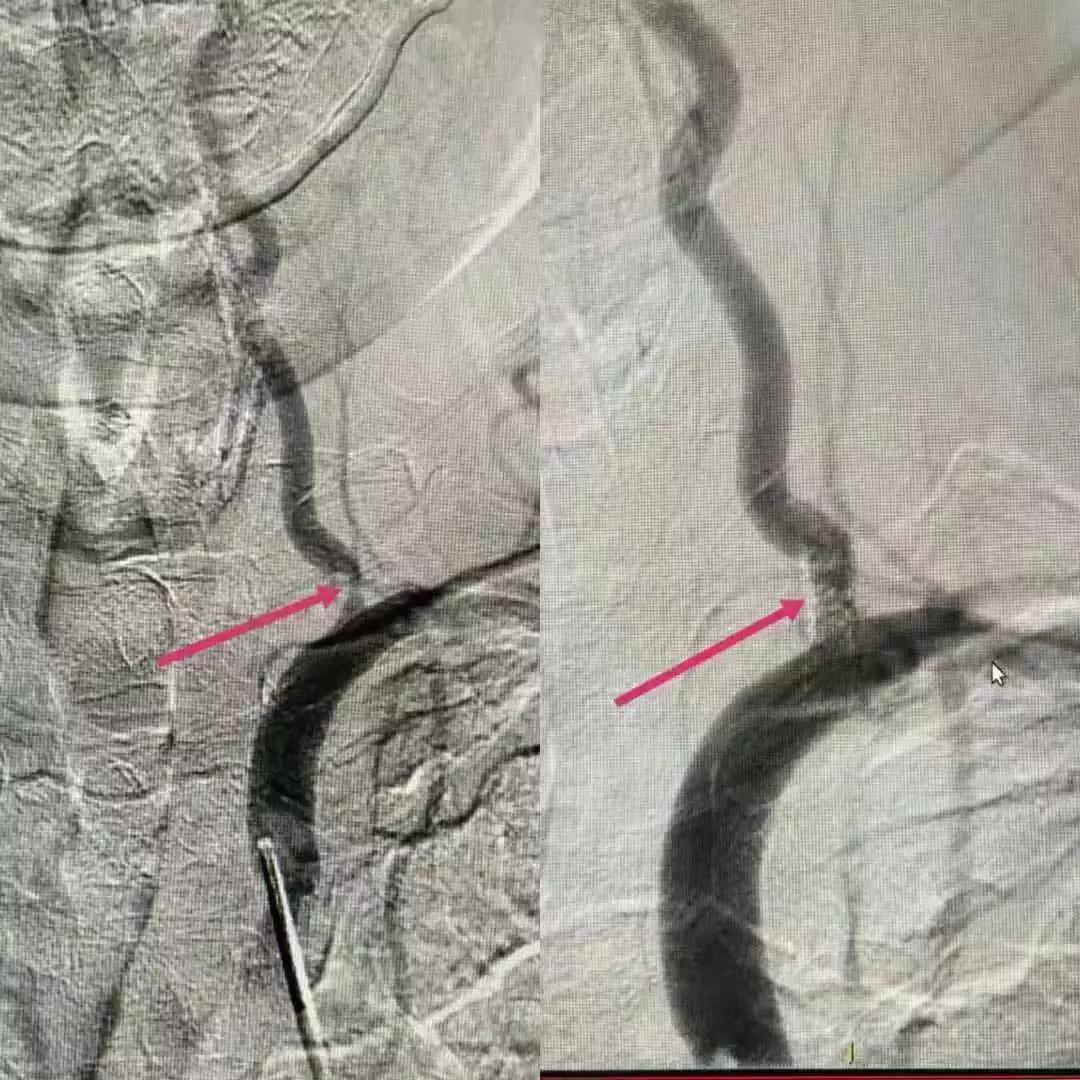

11月5日,我们针对患者手术险、急放药品的准备、术后患者的护理等进行讨论,护士长也积极参加,为术后患者的护理也做着准备,并且认真的标记出需注意的事项,以备对护理人员进行培训。11月6日中午,我们全部人员待命,手术持续一个半小时后于14:40顺利完成左侧颈内动脉、左侧椎动脉支架植入。支架植入术后,患者血管狭窄处管径基本恢复正常,血流通畅,脑灌注良好,患者头量症状消失,术后留院观察期间未再出现肢体麻木无力症状。